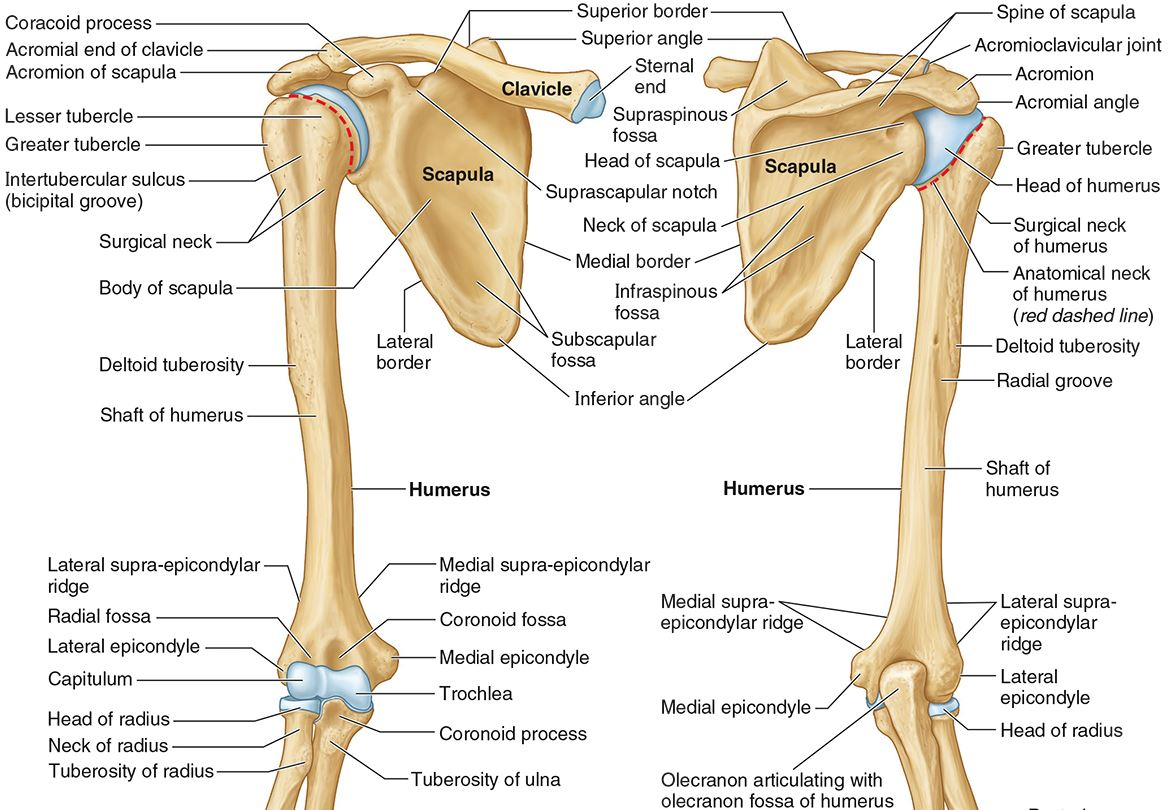

What part of the humerus is this?

The head of the humerus articulates with the scapula at the glenohumeral joint.

What part of the humerus is this?

The anatomic neck is an indentation distal to the head and provides an attachment for the fibrous joint capsule of the glenohumeral joint.

What part of the humerus is this?

The greater tubercle lies lateral and distal to the anatomic neck.

What part of the humerus is this?

The lesser tubercle lies on the anterior/medial side of the humerus, just distal the anatomic neck.

What part of the humerus is this?

The intertubercular (bicipital) groove lies between the greater and lesser tubercles.

What part of the humerus is this?

The surgical neck is a narrow area distal to the tubercles. It is a common site for proximal humerus fractures.

What part of the humerus is this?

The humeral shaft features the deltoid tuberosity laterally for the distal insertion of the deltoid muscle.

What part of the humerus is this?

The radial groove is an oblique depression that contains the radial nerve and deep brachial artery.

Which parts of the humerus is this?

The medial and lateral epicondyles are distal prominences to which many forearm tendons attach, near the elbow joint.

Which parts of the humerus is this?

The medial and lateral supracondylar ridges extend superiorly from the medial and lateral epicondyles.

Which parts of the humerus is this?

The trochlea and the capitulum (the condyles) are the most distal surfaces of the humerus, where it articulates with the forearm bones at the elbow joint

What part of the humerus is this?

The olecranon fossa is a posterior depression above the trochlea that receives that olecranon process of the ulna

What part of the humerus is this?

The coronoid fossa is an anterior depression above the trochlea that receives that coronoid process of the ulna.